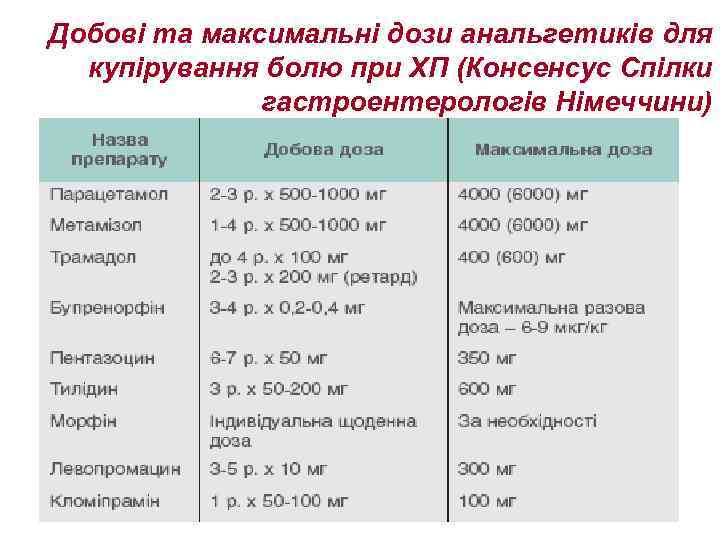

Добові та максимальні дози анальгетиків для купірування болю при ХП (Консенсус Спілки гастроентерологів Німеччини)

Добові та максимальні дози анальгетиків для купірування болю при ХП (Консенсус Спілки гастроентерологів Німеччини)